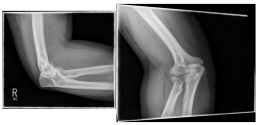

Ellenbogen3

Photo: The fracture on the left is after an operation with a plate and screws